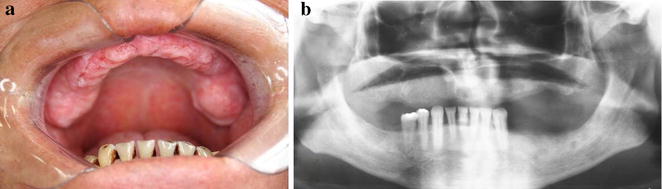

Fig. 4.

Intraoral (a) view and panoramic radiograph (b) showed no bone disease (8 years later during follow-up)

Since the lesion was increasing in size, a second biopsy was performed on a deeper level of histological plan. It showed a proliferation of cells resembling histiocytes with an occasional pale nucleus edentulous with a lobular, grain bean-like appearance (Fig. 2). Microscopic findings and the presence of histiocytic cells led to the performance of an immunohistochemical staining panel using monoclonal antibodies for S-100 (Fig. 3a), CD1a (Fig. 3b), pan-cytokeratin, CD-68, melanoma marker (HMB45) and melanoma A protein. There was positivity for S-100, CD1a, CD-68 and CD45RO (Table 1). Immunohistochemical analysis led to the diagnosis of LCH. We performed a complete investigation, including bone scintigraphy bone, abdomen CT scan; hematological exams, including blood glucose (due to diabetes risk) and a pathological analysis of bone marrow, which was hypercellular without evidence of atypical cells. The liver, spleen and lymph nodes were free of disease. There was no bone involvement besides upper maxilla. The treatment included surgical extraction of all superior teeth, due their periodontal involvement, radiation therapy, corticoid therapies and prosthesis. An established radiation protocol of 26 Gy fractionated over 13 sessions was instituted and well tolerated. We have been following up with the patient for 8 years (2006–2014) without signs of disease recurrence (Fig. 4a and b). At the last follow-up, the patient was considered “disease-free”. Hematological exams, as well as abdomen and chest exams, showed normal conditions.